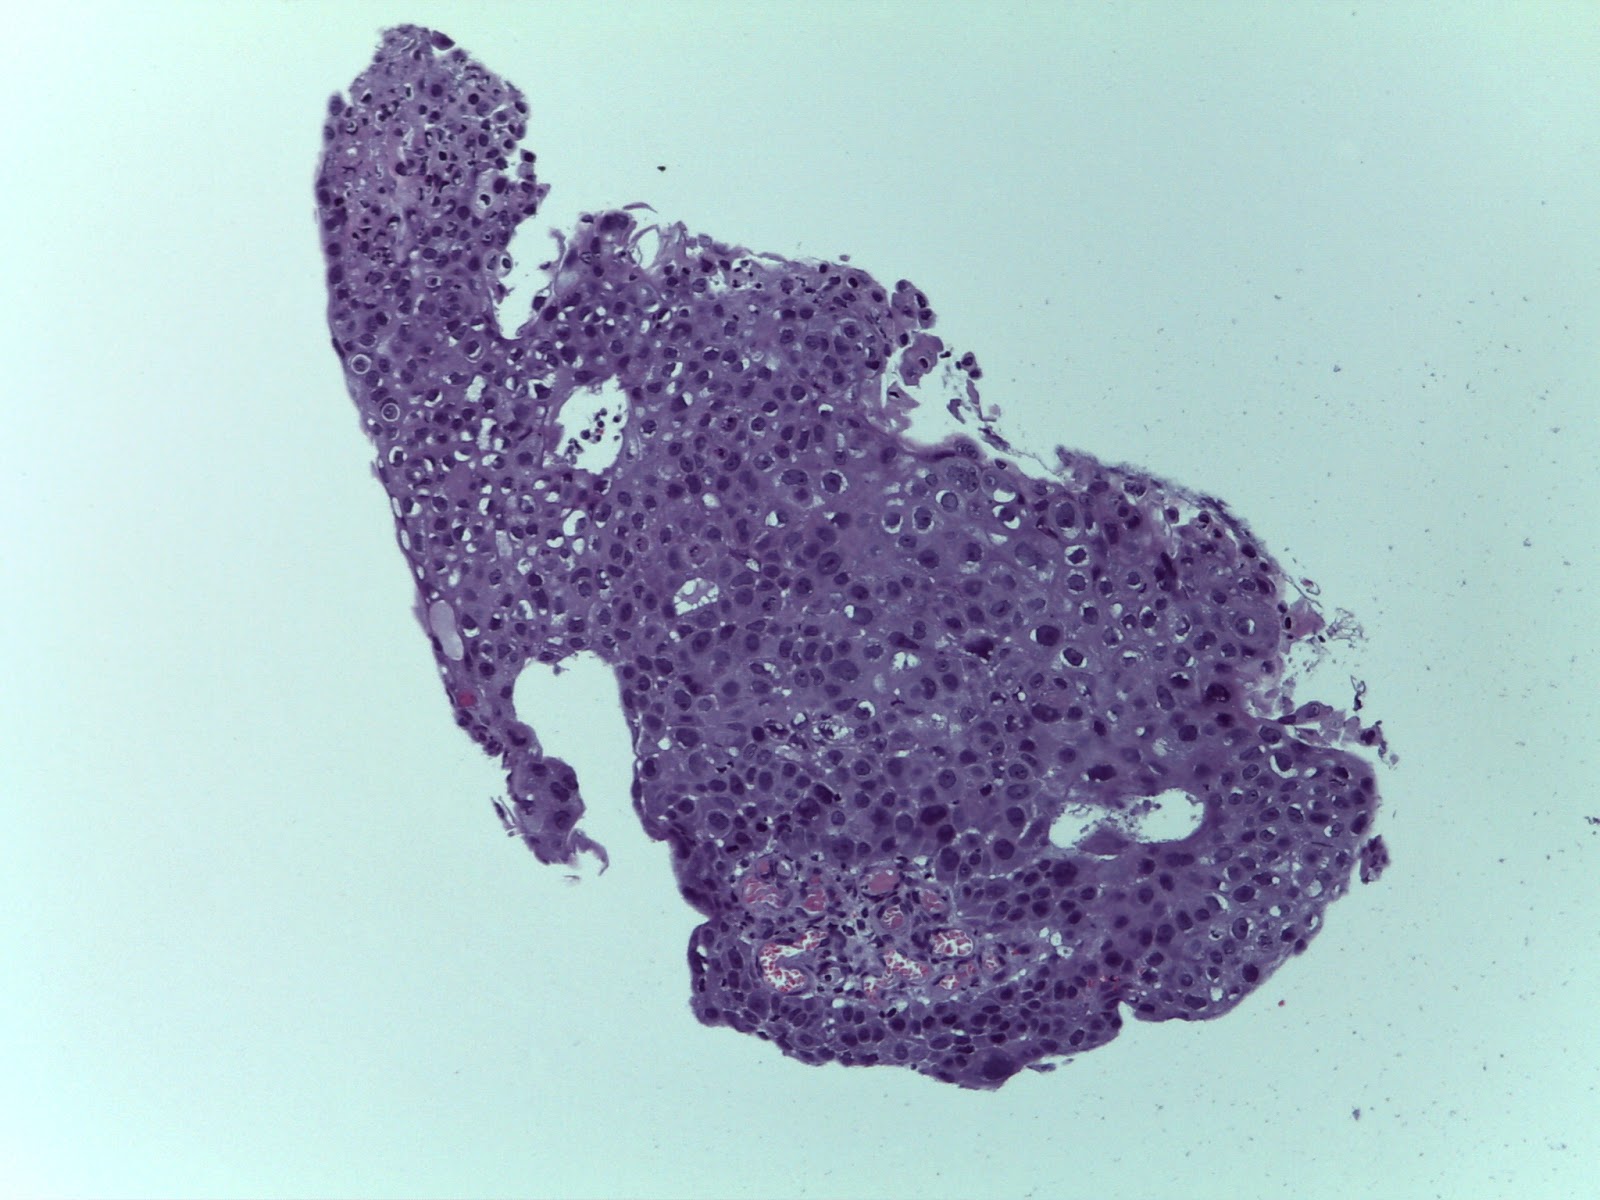

Intermediate Grade Mucoepidermoid Carcinoma This Mucoepidermoid Download Scientific Diagram